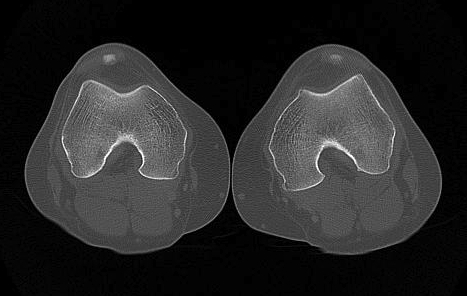

CT

1. Skyline View

Assess for

- lateral tilt

- subluxation

- trochlea dysplasia

2. Lateralisation of tibial tuberosity

Jones et al Skeletal Radiology

Superimpose 2 axial slices

A. Axial slice of trochlea

- line of posterior condyles

- line perpendicular through trochlea

B. Slice through tibial tuberosity

- perpendicular line through TT

Calculate Distance between two points / TTTG

10 - 15 mm normal, > 15 abnormal